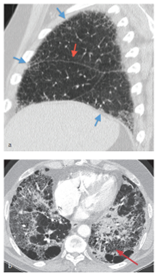

紊乱性纤维化或纤维性瘢痕的临床表现取决于它是发生在局部部位(如瘢痕疙瘩疤痕或手部掌腱膜挛缩症)、影响整个器官(如肝硬化、慢性肾损害或肺间质性疾病)还是全身(如系统性硬化症)。这种影响通常是永久性的,导致相关组织的功能受损。在某些情况下,如特发性肺纤维化(图4),致残性疤痕组织在没有明显炎症的情况下发展。

图4 特发性肺纤维化(IPF)——早期和晚期,自身免疫性疾病的一个例子